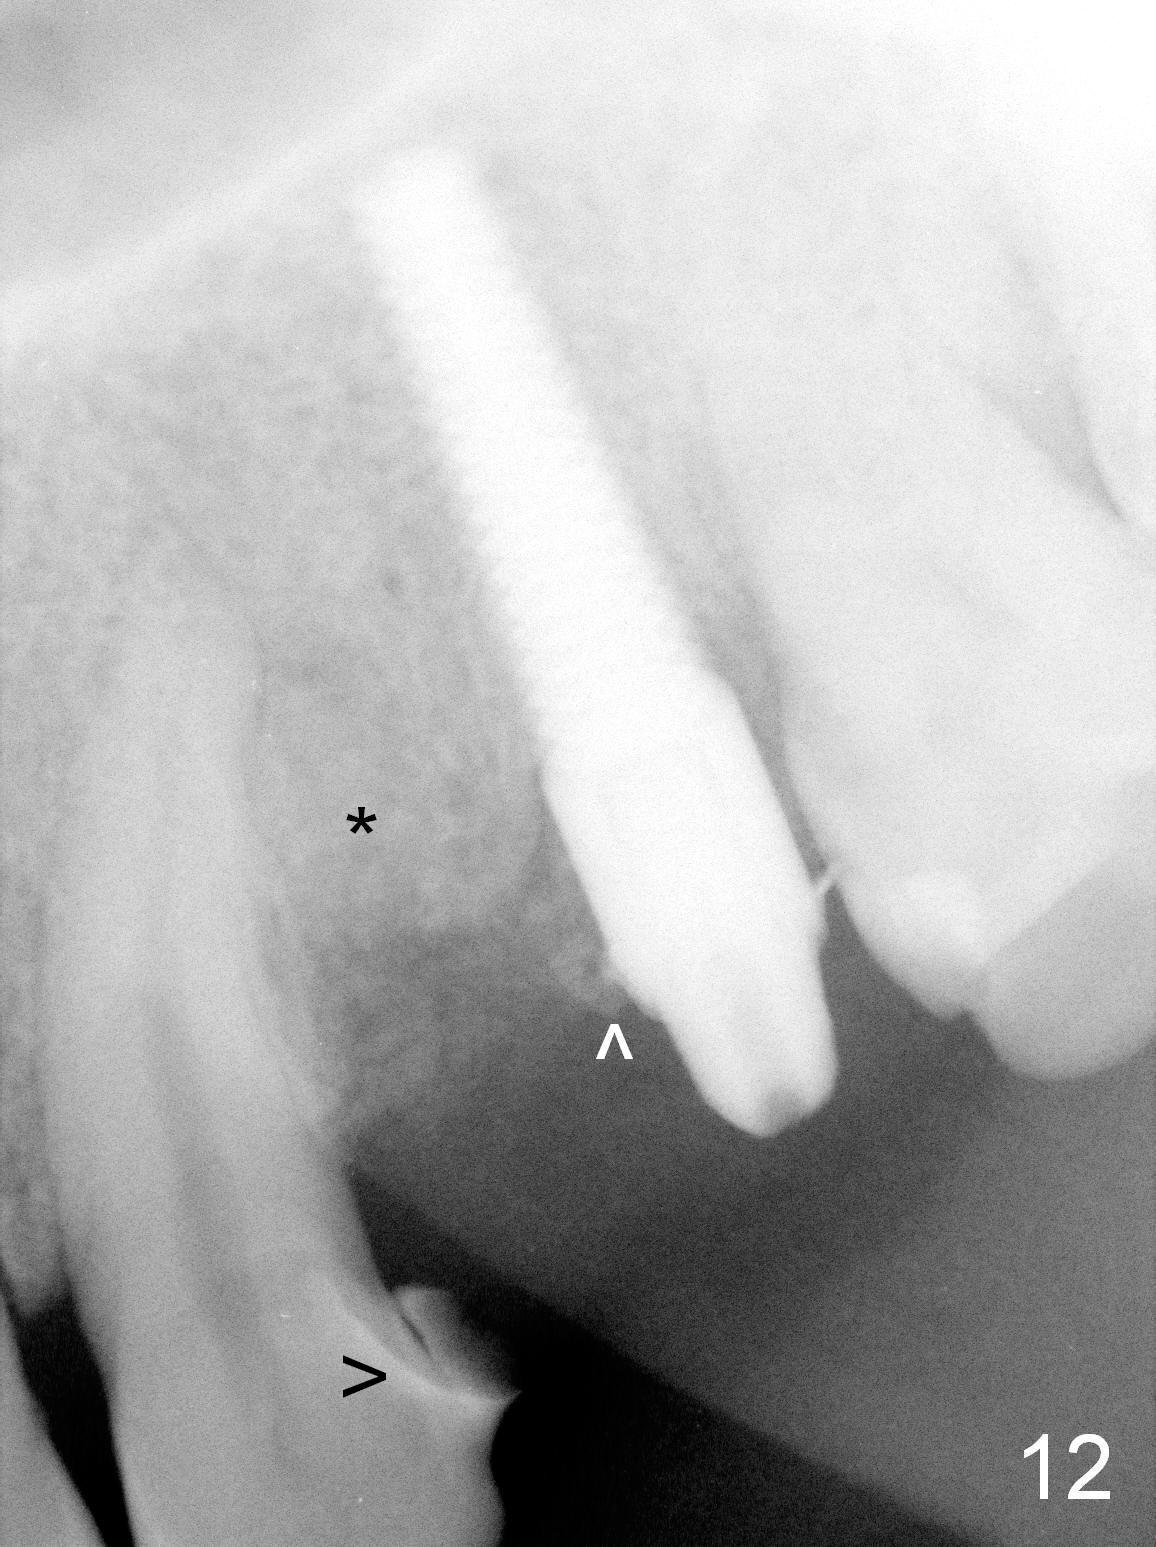

Taking 2 additional PAs with sensor 1 is frustrating (Fig.1,2), no apices shown.  Osteotomy is done smoothly with 2 mm pilot drill at 20 mm, 2.5 mm reamer at 17 mm, and 3 mm reamer at 14 mm and 4.5x20 mm tap at 17 mm.  The 1st intraop PA is taken with sensor 1 when 2 of 4.5x20 mm implants are placed (Fig.3); the implant at #12 is close to the root of the tooth #11.  The 2nd PA is taken with sensor 2: the apex of #11 touches the implant at #12 (Fig.4).  There is no separation when panoramic X-ray is taken (Fig.5).  Effort is exerted to re-direct the osteotomy twice (Fig.6: tap; Fig.7: implant) without success.  When the implant is removed, a PA is taken; it appears that the root of the tooth #11 has no damage (Fig.8).  To obtain the best recovery, socket preservation is carried out with 50/50 cortical/cancellous allograft mixed with Osteogen (Fig.12 *) and Collagen Dressing (Fig.9: #12).  A 2 (or 3)-unit provisional bridge (Fig.10: #12,13) is fabricated over the implant (Fig.9 I)/abutment (A) to cover these 2 sockets.  After acid etching #11 D surface (Fig.9 >) and relining (Fig.11 *), the provisional bridge is bonded to the tooth #11 (Fig.11,12 black >) so that bone graft will be less likely dislodged.